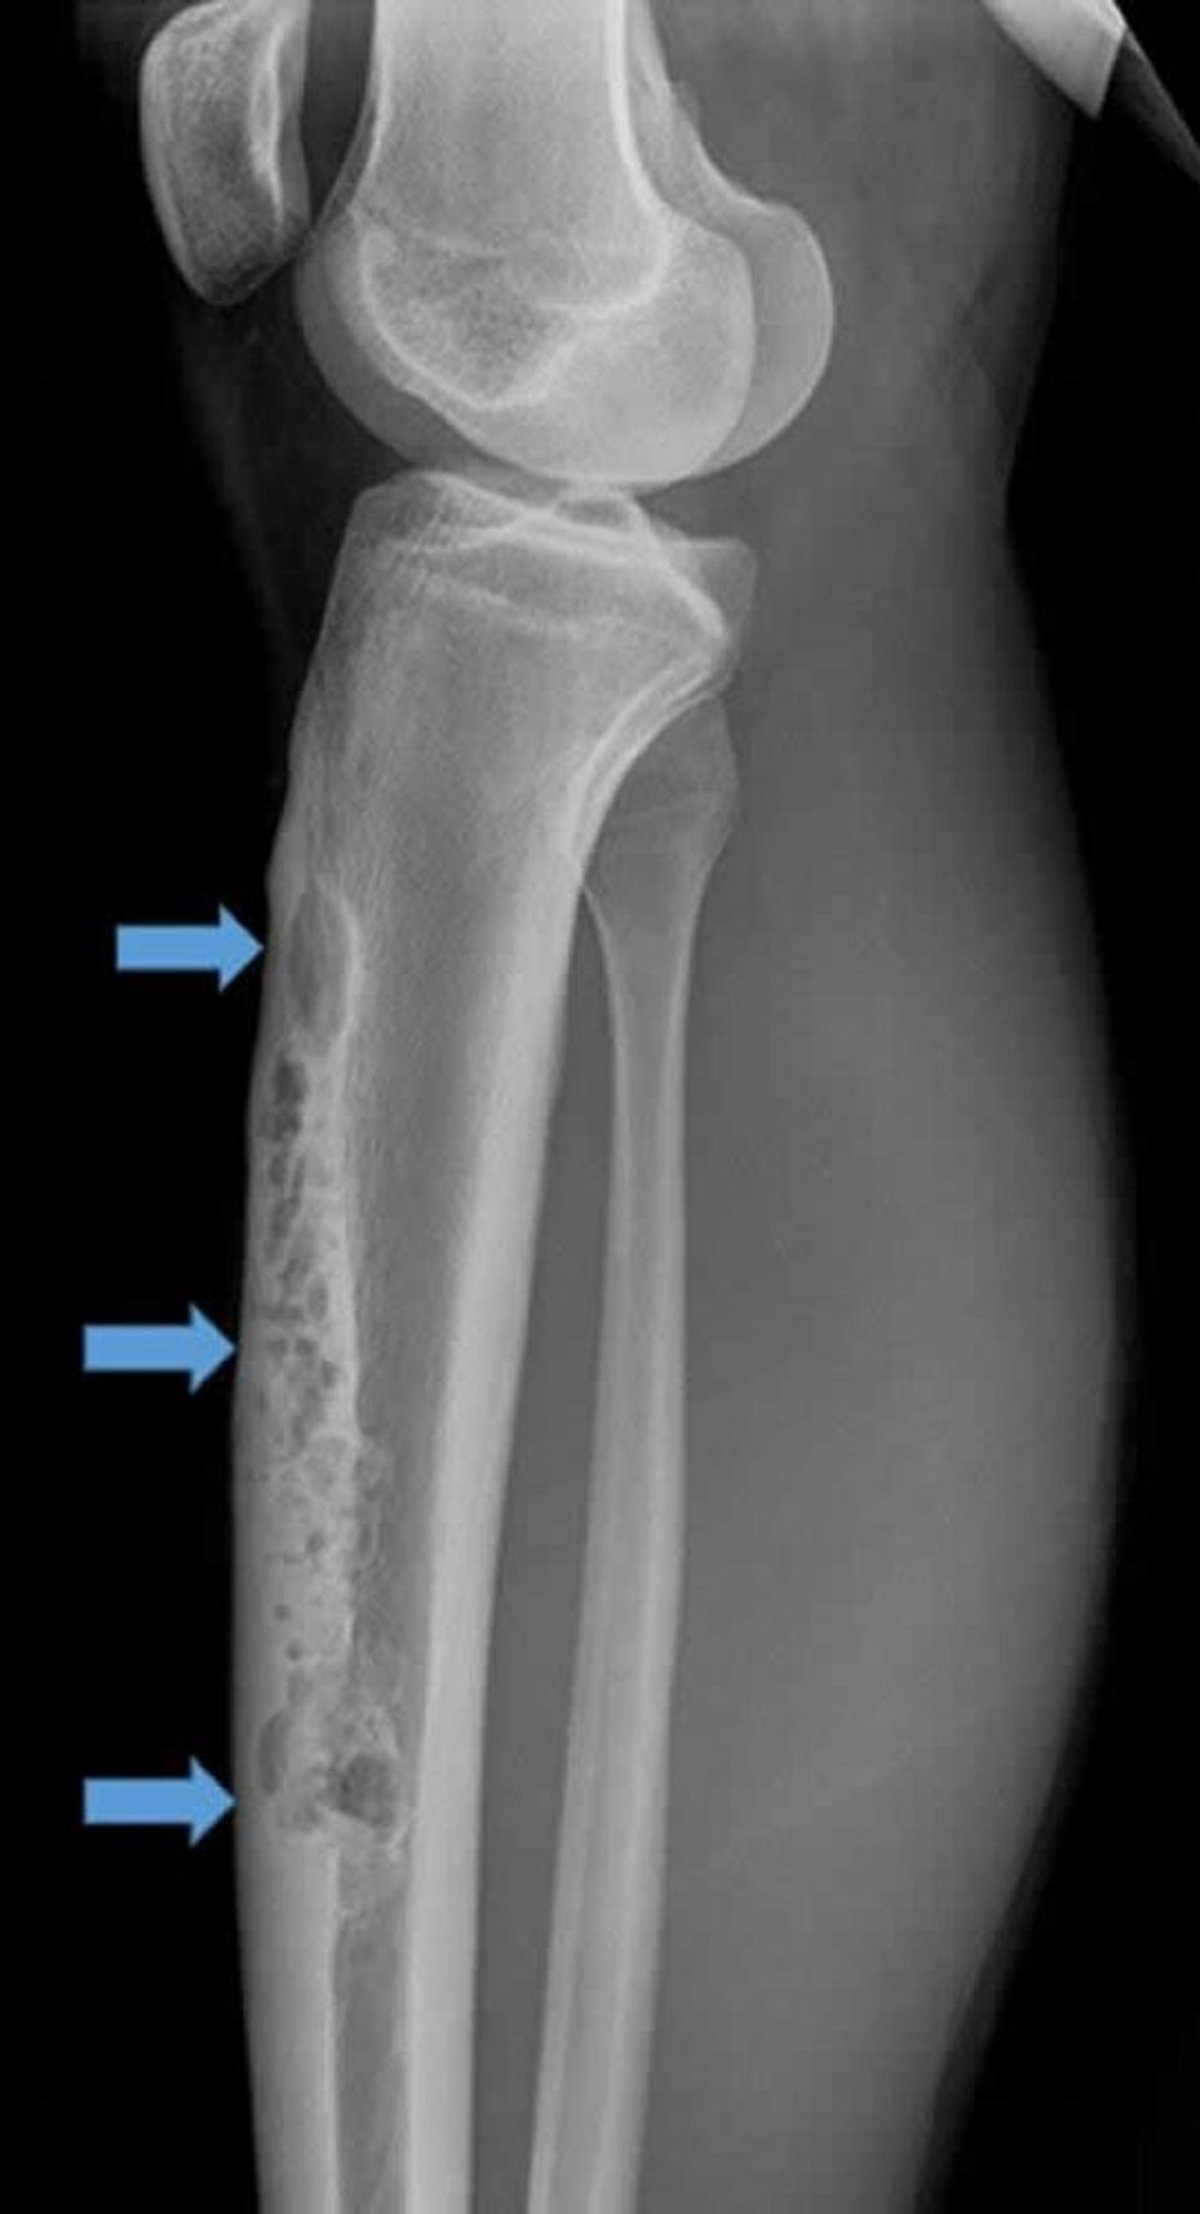

Questa radiografia di profilo della tibia destra mostra un ampio adamantinoma intracorticale anteriore (frecce). Si noti l'aspetto permeativo e osteolitico "a bolle di sapone".

Image courtesy of Michael J. Joyce, MD, and Hakan Ilaslan, MD.